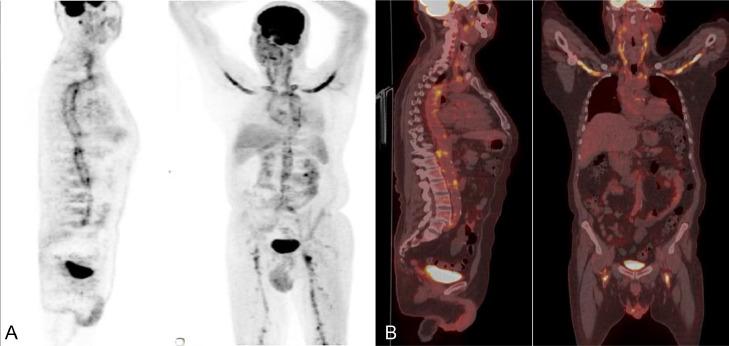

Giant cell arteritis (GCA) is a rare form of large and medium vessel vasculitis affecting about 20 cases per 100,000 persons older than the age of 50 years. GCA results in inflammation and constriction of the temporal arteries, cranial arteries, the aorta, and its major branches. Patients often present with vague constitutional symptoms and fever of unknown origin. GCA is a medical emergency requiring prompt diagnosis and early treatment with glucocorticoids which is essential to avoid irreversible end organ damage such as loss of vision, stroke and aneurysm formation. We report a case of a 63-year-old male patient presenting to our healthcare facility with sudden loss of vision and an ischemic brain infarct to be finally diagnosed as a case of giant cell arteritis with positron emission tomography-computed tomography imaging used to evaluate the full extent of the involved vasculature. Diagnostic imaging with FDG positron emission tomography-computed tomography can play a crucial role in the diagnosis, evaluation of the full burden of the disease and follow up to the response of therapy.

巨细胞动脉炎(GCA)是一种罕见的大中血管血管炎,在50岁以上人群中,每10万人中约有20例发病。GCA会导致颞动脉、颅动脉、主动脉及其主要分支发生炎症和狭窄。患者常出现不明原因的全身症状和发热。GCA是一种医疗急症,需要迅速诊断并尽早使用糖皮质激素治疗,这对于避免不可逆转的终末器官损害(如视力丧失、中风和动脉瘤形成)至关重要。我们报告一例63岁男性患者,因突然视力丧失和缺血性脑梗死前来我院就诊,最终经正电子发射断层扫描-计算机断层扫描成像确诊为巨细胞动脉炎,该成像用于评估受累血管系统的全貌。使用氟代脱氧葡萄糖正电子发射断层扫描-计算机断层扫描进行诊断成像在疾病的诊断、评估疾病的整体负担以及随访治疗反应方面可发挥关键作用。